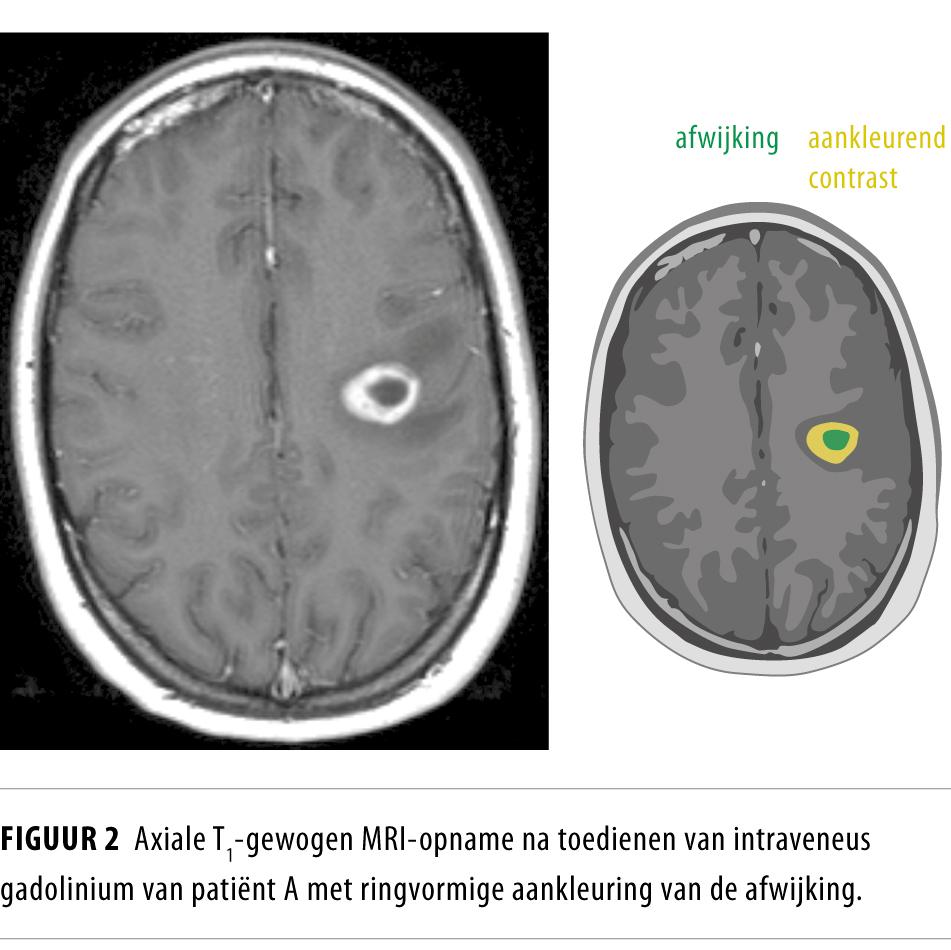

Casus

Wij presenteren een 20-jarige patiënte die de huisarts bezocht vanwege een licht afhangende mondhoek rechts. De huisarts startte behandeling met orale glucocorticoïden vanwege een vermeende idiopathische perifere aangezichtsverlamming en verwees haar naar de polikliniek Neurologie. Bij herhaald neurologisch onderzoek bleek er sprake van een centrale facialisparese rechts. Een MRI van het cerebrum toonde een grote aankleurende afwijking in de linker hemisfeer. Na uitgebreid aanvullend onderzoek werd de waarschijnlijkheidsdiagnose ‘TDL’ gesteld. Gezien de geringe klinische verschijnselen werd een expectatief beleid gevoerd. Patiënte herstelde spontaan en herhaald MRI-onderzoek toonde partiële regressie van TDL.

TDL wordt vaak beschouwd als een eerste presentatie van multipele sclerose. Nauwkeurige analyse met MRI-onderzoek kan helpen de diagnose te stellen zonder dat biopsie noodzakelijk is.